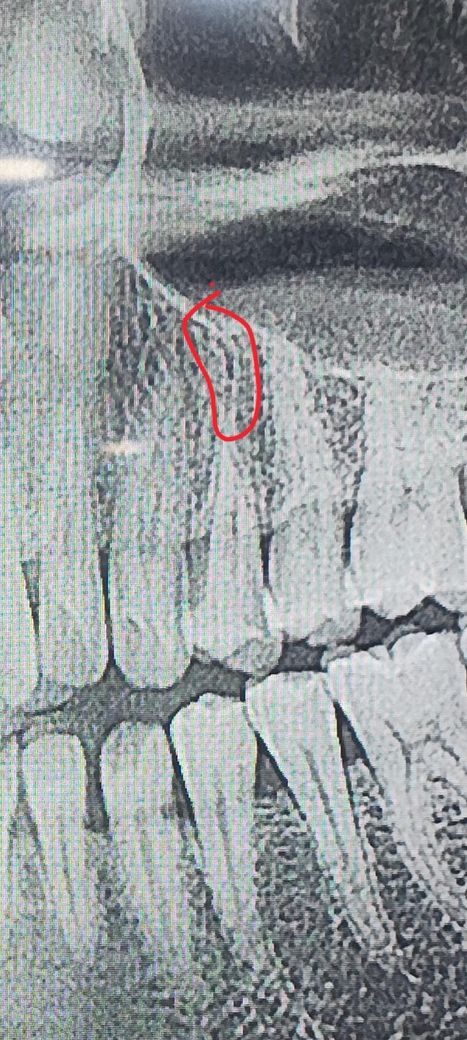

치아파절 된건지 엑스레이보시고 답변 부탁드려요

엑스레이사진상 동그라미 해당하는 부위 검은 선

같은게 있는데 혹시 이거 세로로 치아 파절된건가여??

뽑아야 할까요?? 이선의 정체가 궁금합니다

표시해주신 것은 치아의 뿌리입니다. 해당치아는 볼쪽과 입천장 쪽으로 뿌리가 각 1개씩 총 두개가 있는 치아인데 엑스레이는 평면으로만 표현이 되기 때문에 두개의 뿌리가 겹쳐져서 그렇기 보이는 것입니다. 그리고 파절선은 파노라마에 쉽게 보이지 않고, 만약 파노라마에 보일만큼의 파절이라면 엄청 아프셨을겁니다.

치근 파절로 보이진 않습니다. 해당 치아의 neurovascular canal 로 보입니다. 정상구조입니다.